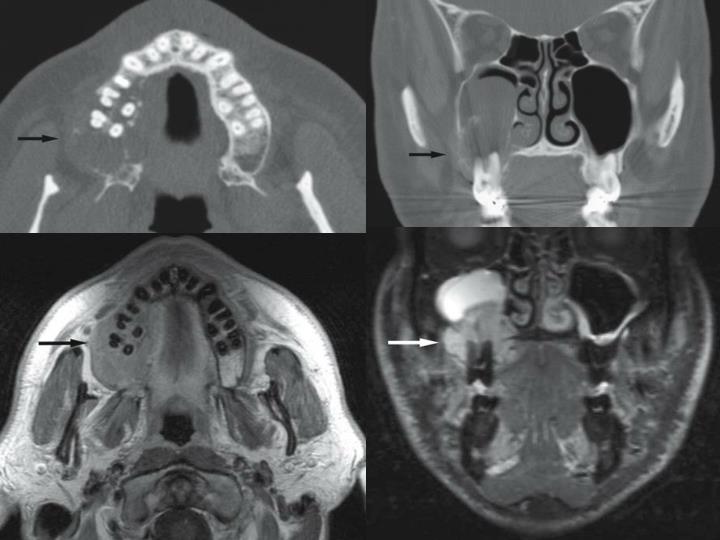

Imaging Characteristics of Benign, Malignant, and Infectious Jaw Malignant Tumor Jaw Bone A person with jaw bone cancer develops a malignant tumor on their mandible, lower jaw bone, or maxilla, which is the hard palate or upper jaw bone. Tumors that arise in the jaw can be either malignant or benign and are called odontogenic tumors. Jaw bone cancer can develop in the bone. Osteosarcoma (os) accounts for about 20% of all. Malignant Tumor Jaw Bone.